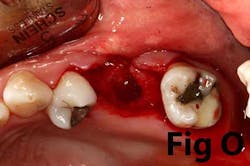

There is an abundance of literature showing increased gingival inflammation around natural dentition (exacerbated when a fixed restoration is present) when there is less than 2 mm AG. (Figs. 8, 9: post grafting) There is an abundance of literature showing increased incidence of peri-implant mucositis when there is inadequate attached tissue — a weaker connective tissue adhesion and lack of Sharpey’s fibers make the peri-implant tissue even more susceptible to bacterial challenge. (1-6, 8, 10) And as periodontitis is always preceded by gingivitis, peri-implantitis will be preceded by peri-implant mucositis. If we can decrease the incidence of peri-implant mucositis by providing a better and more resilient tissue phenotype, we can lower the incidence of peri-implantitis.The FGG procedure is indicated in cases of implant therapy where this is less than 2 mm of attached tissue present. Sometimes, a FGG is preferred over CTG because: (1) the FGG results in greater gain of attached tissue, (2) the FGG alleviates frenum/muscular pull whereas the connective tissue may increase muscular tension after the flap is coronally advanced, and (3) creeping attachment is often a positive byproduct of the FGG procedure.

Refer to Case Nos. 1 & 2.

Case No. 1